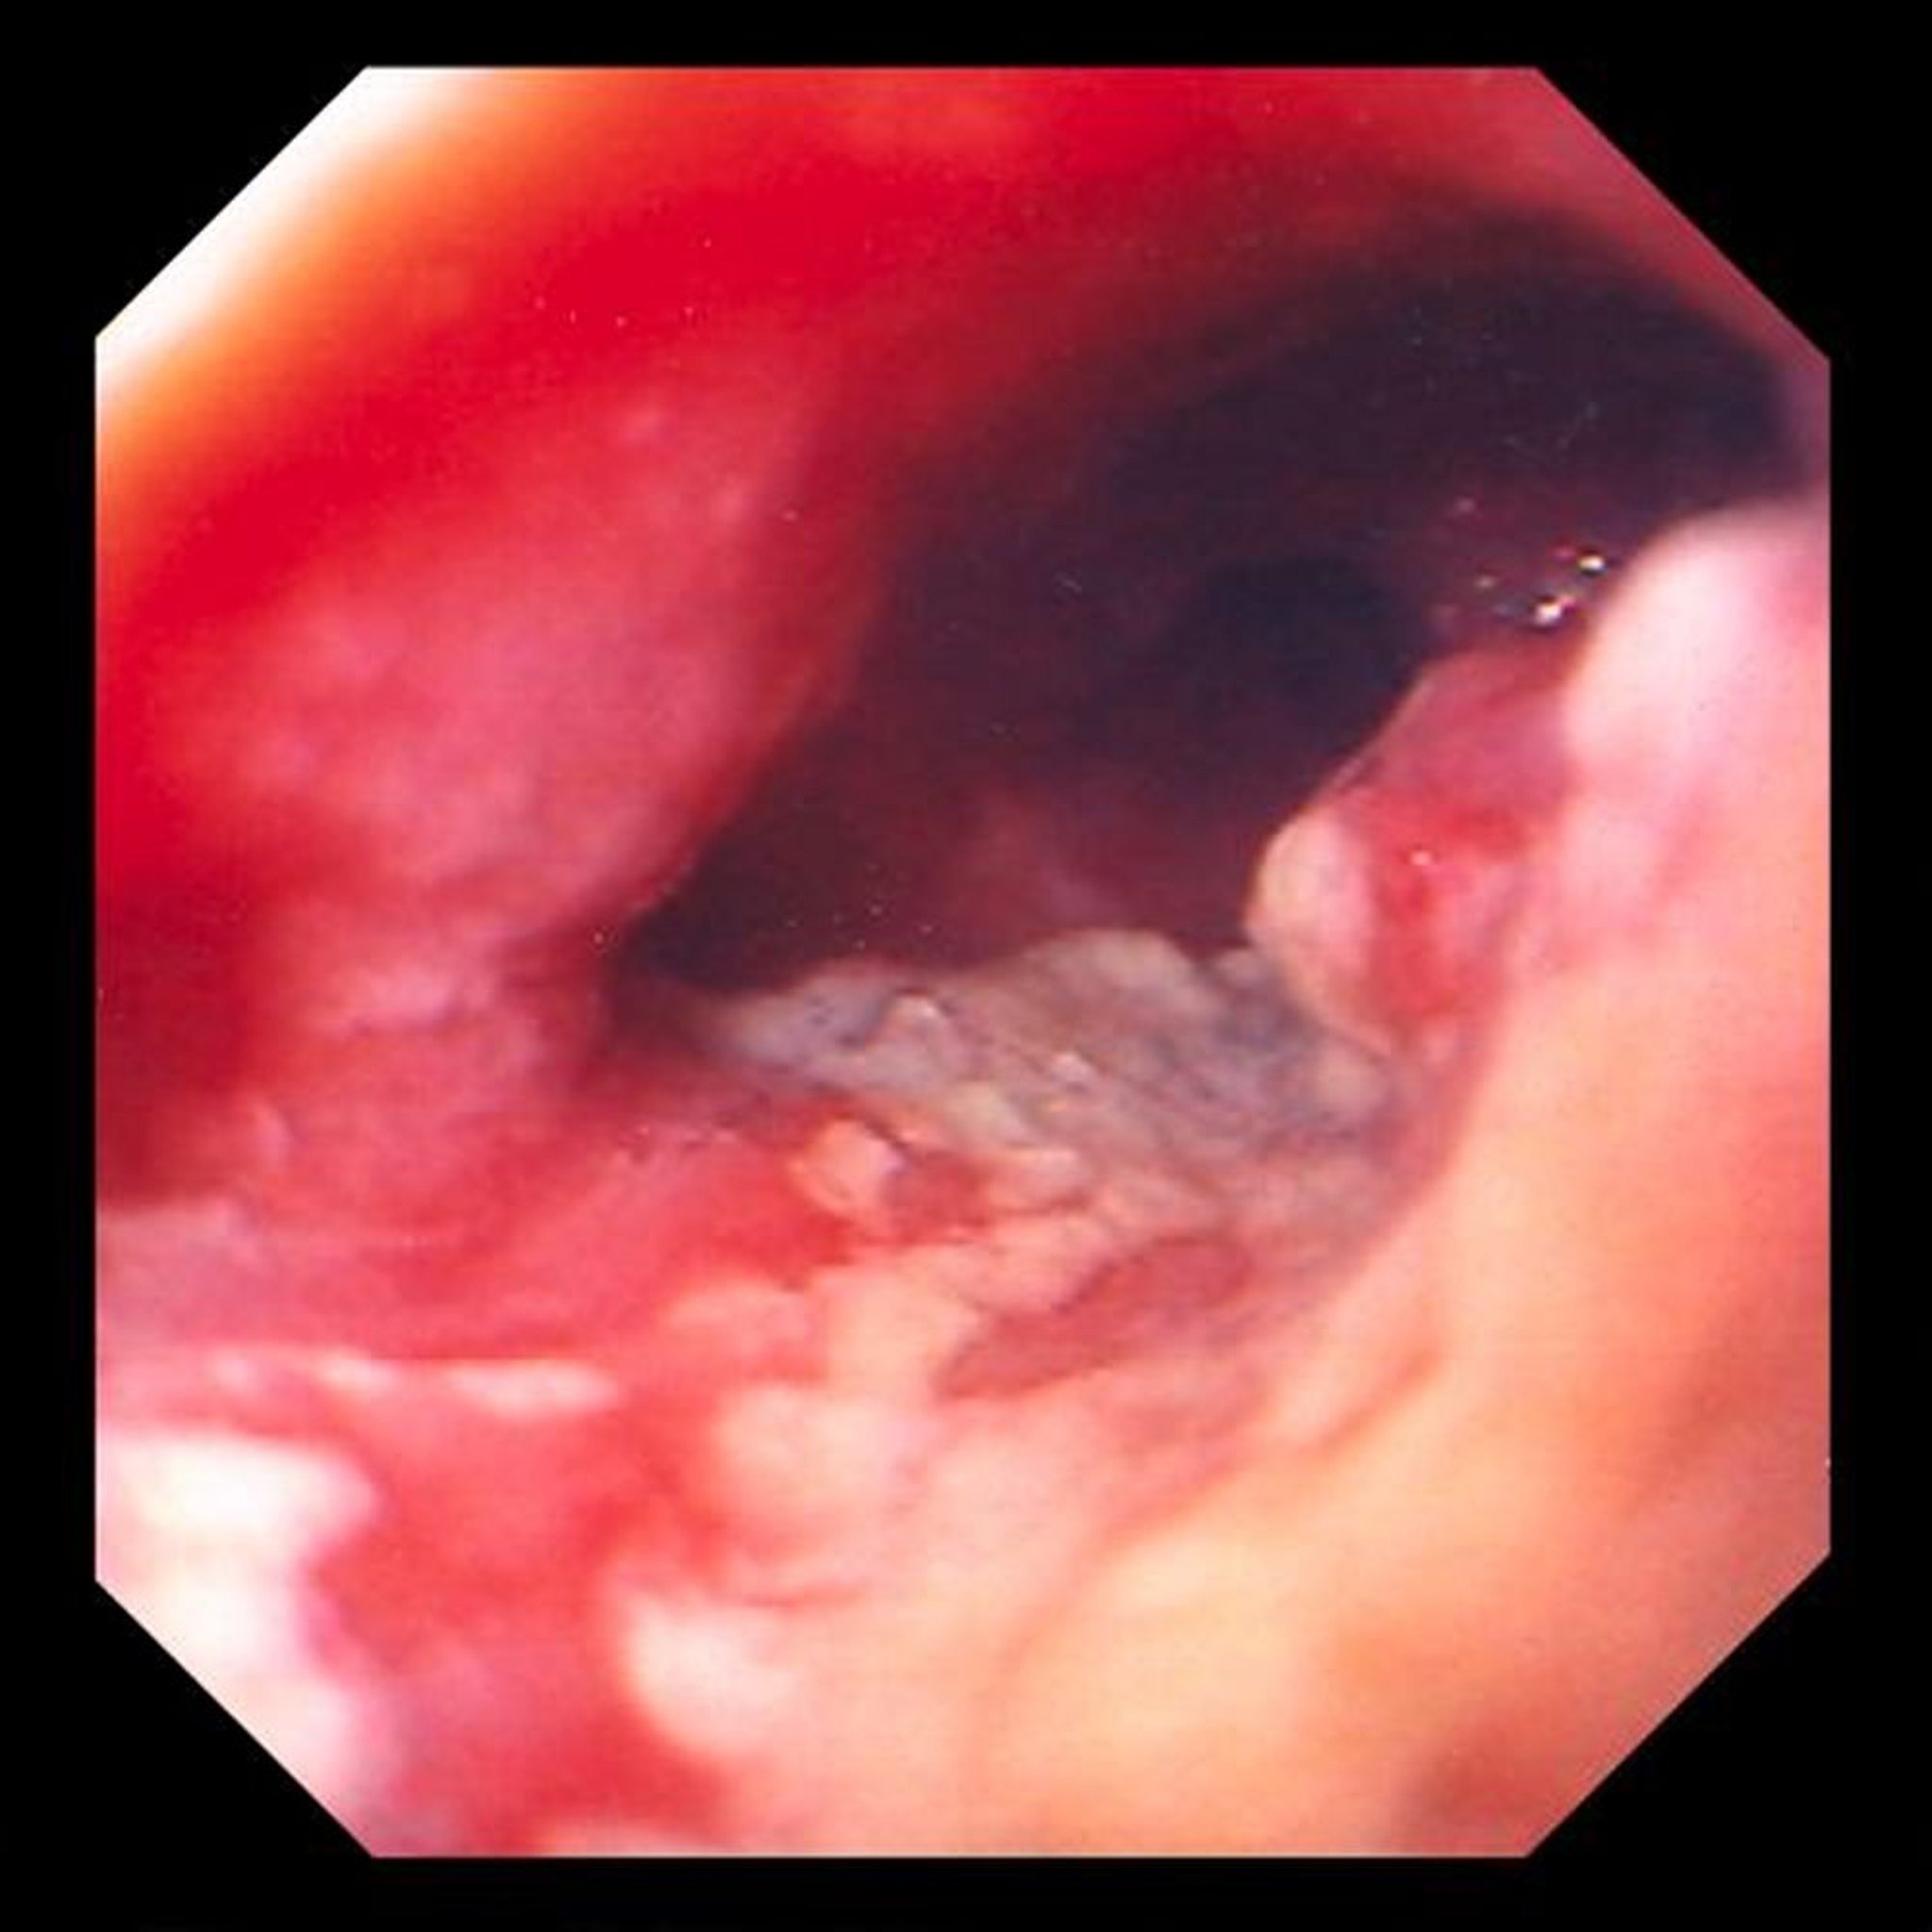

Adenocarcinoma de esófago

Esta imagen muestra un tumor ulcerado y constrictivo localizado en el segmento distal del esófago, que es altamente sugestivo de adenocarcinoma, originado a partir de cambios cilíndricos metaplásicos (esófago de Barrett).

Image provided by David M. Martin, MD.